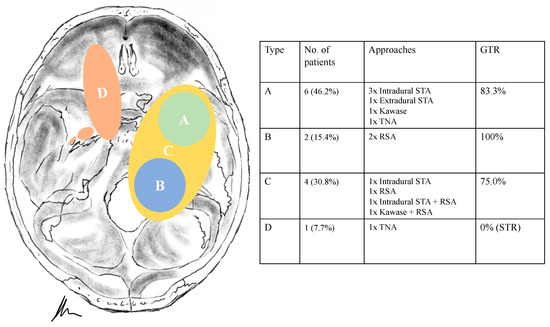

Different classifications have been described in the literature [3,4,5,6,7]. Samii et al. proposed a simplified and useful division into four categories based on radiological findings, whereas Ramina et al. added modifications according to the level of difficulty, describing also two-stage approaches for the most difficult so-called “Type F” tumors [5,6] (Figure 2).

Tumour locations were classified according to Samii’s and Ramina’s classification [5,6]. According to Samii et al. (Table 2), six schwannomas were classified as Type A, two as Type B, four as Type C and one as Type D. In two cases, the tumor was resected in a two-stage technique. The intradural subtemporal approach was performed in five cases, the extradural technique once, the retrosigmoid in five cases, the Kawase and a transnasal approach in two cases, respectively. The two cases with a two-stage approach (one neurofibromatosis type 2 (NF2) patient, Figure 1) were classified as Type E, according to Ramina et al., reflecting the surgical difficulty [6].

Treatment strategy for trigeminal schwannomas should always respect the individual’s anatomy, clinical presentation and the patient’s baseline characteristics. As already described, diverse classifications have been proposed to facilitate decision making and assess the technical difficulty [3,4,6,11,20,21,22]. However, we believe the choice is mainly whether the tumor has to be approached via a posterior or a middle/anterior fossa approach. Thus, the basic division made by Samii et al. puts the options in a nutshell with following classification [5]: Type A, intracranial tumor predominantly in the middle fossa; Type B, intracranial tumor predominantly in the posterior fossa; Type C tumors in the middle and posterior fossa and Type D extracranial tumor with intracranial extensions.

Type A, C and D tumors can be targeted via a middle fossa approach, whereas Type B tumors are well managed through a retrosigmoid technique; in case of Type C tumors, a combined approach may be mandatory (Figure 1). Size of the tumor, goal of the surgery (biopsy, cranial nerve decompression, GTR) and the characteristics of the tumor must be considered. Type D tumors have a separate strategic position, as the extradural and extracranial portion of the schwannoma define the approach, ranging from an extradural subtemporal approach, an anterior/posterior petrosectomy to (endoscopic) transfacial or transnasal techniques [1,4,6,8,10,12,16].

Figure 2. Illustration (according to Samii) and overview of the classification systems of trigeminal schwannomas.

Figure 8. Illustration displaying surgical techniques and outcomes for each tumor type (according to Samii). STA = Subtemporal approach. TNA = Transnasal endoscopic approach. RSA = Retrosigmoid approach. GTR = Gross total resection. STR = Subtotal resection.